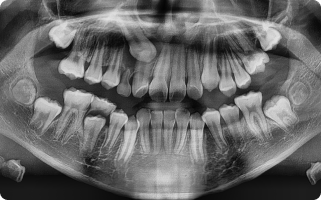

함치성 낭종은 나지 않은 치아(주로 사랑니, 송곳니) 주위에 생기는 물주머니(낭종)입니다.

치아가 잇몸 속에서 올라오지 못하고 머물면서 그 주위에 액체가 고여 발생합니다.

- 흔히 사랑니나 매복된 송곳니에서 발견됩니다.

- 크기가 커지면 주변 뼈를 흡수하거나, 옆 치아 뿌리를 밀어 손상시킬 수 있습니다.

- 대부분 통증이 없어 정기적인 X-ray 검사에서 우연히 발견되는 경우가 많습니다.

- 국소마취 후 잇몸을 열어 낭종과 함께 원인 치아를 제거합니다.

- 낭종 벽을 깨끗이 적출하여 재발을 막습니다.

- 병리검사를 통해 정확한 진단을 확인합니다.

- 작은 경우는 간단히 제거가 가능하고, 큰 경우는 단계적으로 치료하기도 합니다.